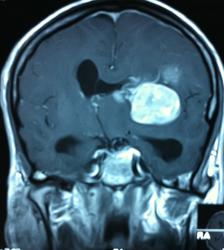

Начало вот здесь http://www.radiomed.ru/cases/kt-gms-obemnoe-obrazovanie-levoi-gemisfery-bolshogo-mozga-vnutrizheludochkovaya-meningioma. Пациент оперирован (меня сначала дезинформировали по поводу операции), перед операцией состояние ухудшилось, возникла правосторонняя гемиплегия, которая осталась и после декомпрессии. МРТ, КТ снимки и выписку предоставила супруга пациента, снимал на iphone, простите за качество, дисков с исследованиями не записывали. Надеюсь вопрос по данному случаю исчерпан.

Вот "цветочки":

FLAIR

И Вы считаете, что эта опухоль имеет интравентрикулярную локализацию?

Изначально по КТ я так предпологал, а теперь на 100% уверен, разве МРТ это не показало? Гистологически - менингиома, опухоль мозговой оболочки. Покажите, пожалуйста, образование где-нибудь прилежит к костям, где есть мозговая оболочка? Я не вижу, зато отчетливо вижу в левом боковом желудочке из оболочек сосудистого сплетения. Что вас еще смущает? По-моему, предостаточно фактов, чтобы развеять все сомнения.

Мне видится так. Иначе в данной локализации просто неоткуда расти оболочечной опухоли. На контрольной КТ, после декомпрессии, когда срединные структуры стали действительно срединны, правое обызвествленное сосудистое сплетение видно отчетливо, а левое, где оно? Ведь если бы образование компремировало, то после операции, когда часть мозга пролабировало в трепанационное отверстие мы бы увидели и левое сосудистое сплетение, но оно интимно связано с образованием и даже "потянулось" за ним в сторону декомпрессионного отверстия, потому что это и есть "росток" откуда выросла опухоль.